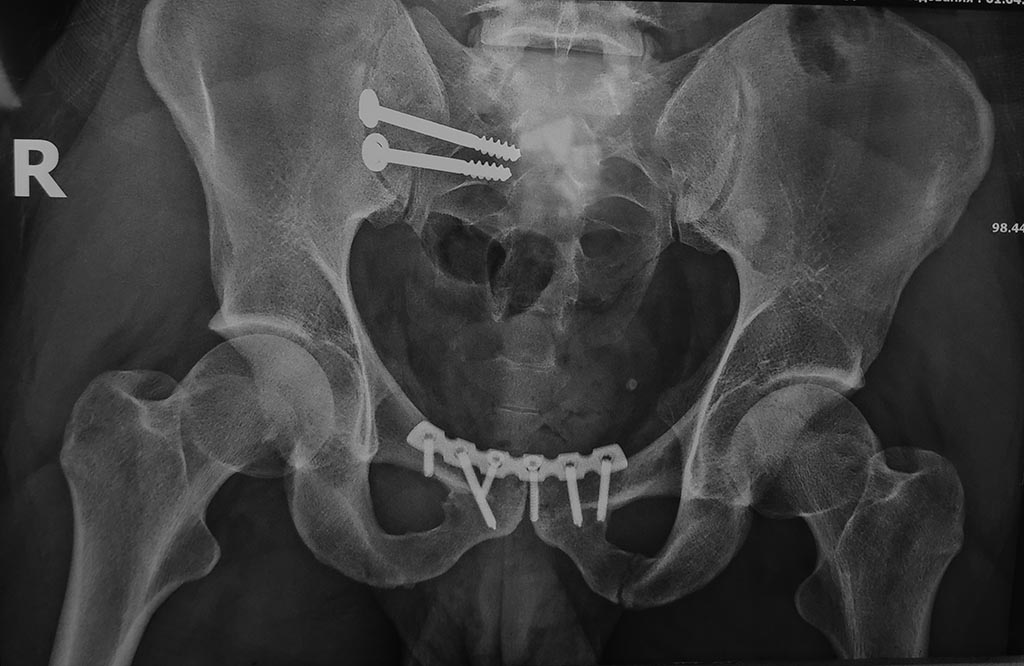

Повреждение таза после ДТП

такая вот травма таза при ДТП, интересно что при таком расхождении лона мочевой пузырь остался целым

вид после

В месте внутренней крестцово-подвздошной связки большая гематома. седалищный нерв в гематоме.